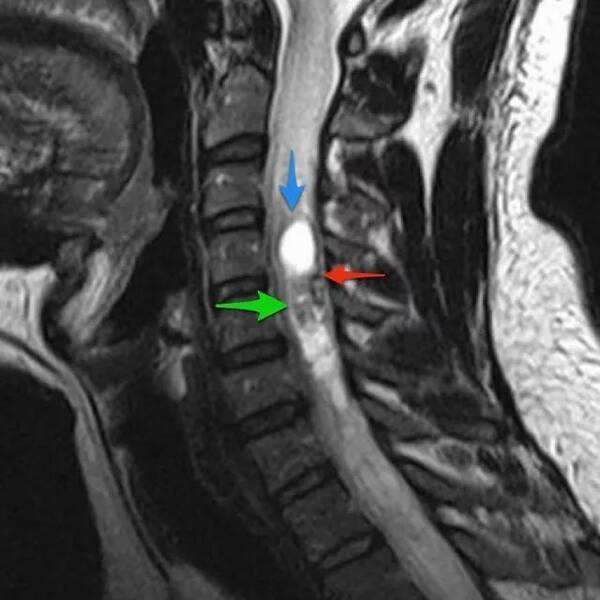

炎症和高信号,在核磁共振上,尤其是在核磁T2的影像上,就能看到白花花的骨髓水肿了。一般来说从我们学科上来说,就是比较单纯的,硬力外力所导致的,过性的创伤。所以说不用太过担心。